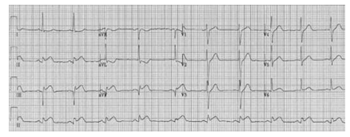

Um paciente de 62 anos de idade, previamente hipertenso, apresentava dor torácica típica já há 2 horas, irradiando para o braço esquerdo, associada à sudorese e às náuseas. No exame físico, apresentava-se estável hemodinamicamente. O eletrocardiograma de admissão está disposto logo a seguir. O paciente chegou ao serviço médico às 19 horas, na troca de plantão, passando-se, assim, 45 minutos sem reavaliação. O paciente estava em um hospital sem serviço de hemodinâmica, e o centro de referência mais próximo tinha um tempo estimado de recebimento do paciente em 80 minutos.

Com base nesse caso clínico hipotético, assinale a opção que apresenta a conduta adequada.